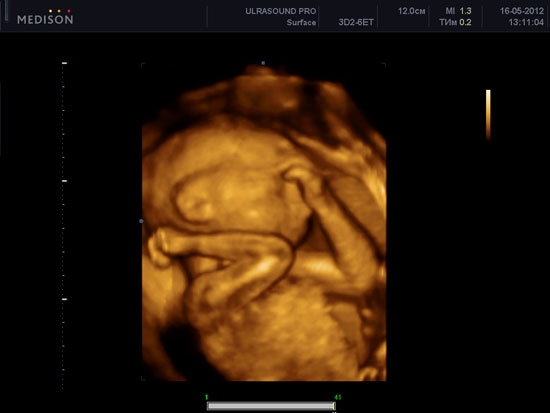

УЗИ (ультразвуковое исследование) — важный инструмент для наблюдения за развитием беременности, позволяющий родителям увидеть малыша на разных этапах. В статье представлены фото УЗИ по неделям беременности, что поможет понять изменения в ребенке и обсудить ключевые моменты с врачом. Эти изображения визуализируют развитие плода и предоставляют информацию о его здоровье, что делает их незаменимыми для будущих мам и пап.

Врачи подчеркивают важность ультразвукового исследования на разных этапах беременности. УЗИ позволяет не только подтвердить факт беременности, но и отслеживать развитие плода, выявлять возможные аномалии и оценивать состояние матери. Специалисты отмечают, что каждое исследование имеет свои особенности в зависимости от срока. На ранних сроках УЗИ помогает увидеть сердцебиение и определить количество эмбрионов. Позже, на более поздних сроках, врачи могут оценить анатомию плода, его размеры и положение в матке. Фотографии, полученные во время УЗИ, становятся важной частью медицинской документации и часто вызывают эмоциональный отклик у родителей. Врачи рекомендуют проходить УЗИ в установленные сроки, чтобы обеспечить здоровье как матери, так и ребенка.